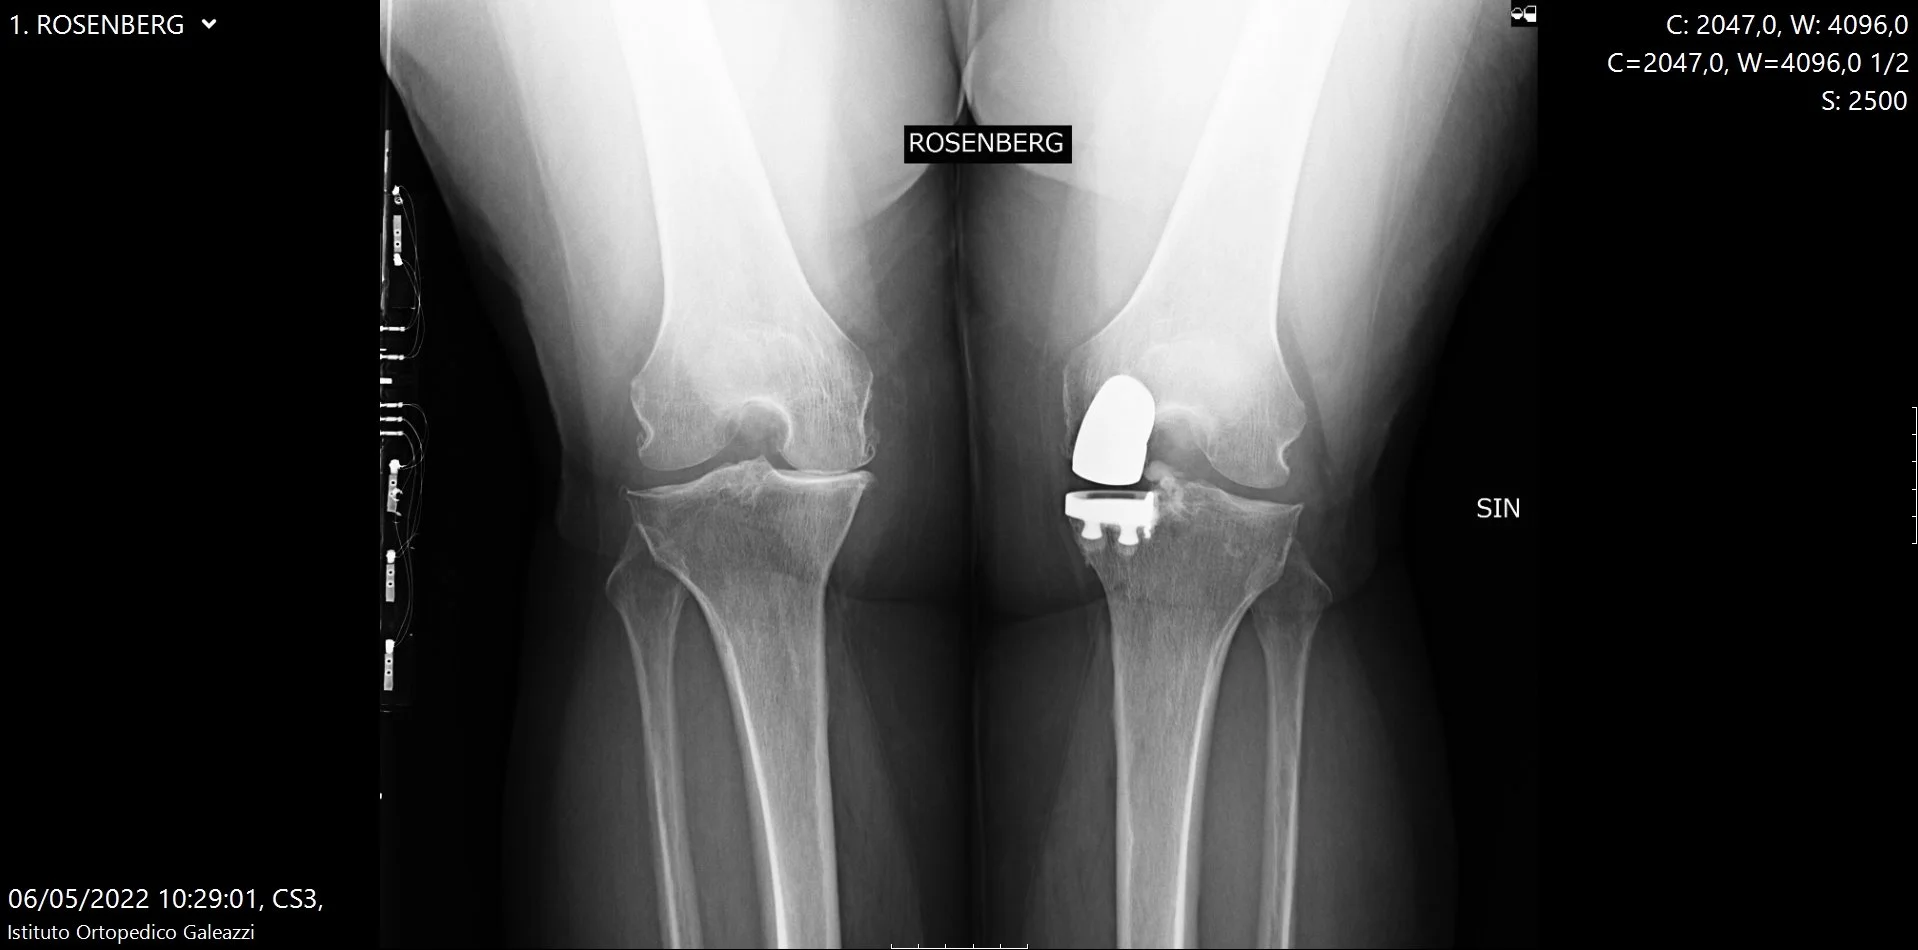

La proiezione di Rosenberg è una radiografia del ginocchio eseguita sotto carico, con il paziente in posizione eretta e il ginocchio flesso di circa 45 gradi.

Questa proiezione consente una migliore visualizzazione delle superfici articolari posteriori, spesso coinvolte nelle fasi iniziali o intermedie dell’artrosi.

In particolare, la proiezione di Rosenberg permette una visualizzazione più accurata del compartimento femoro-tibiale posteriore, cioè l’area dove, molto spesso, iniziano i primi segni di degenerazione cartilaginea nell’artrosi del ginocchio.

Cosa mostra meglio rispetto alla radiografia tradizionale

Nella radiografia standard antero-posteriore (AP) in estensione, lo spazio articolare può apparire ancora relativamente conservato, soprattutto nelle fasi iniziali della malattia.

Con la flessione del ginocchio a 45°, invece:

• il carico si concentra sulle aree posteriori delle superfici articolari

• eventuali riduzioni dello spazio articolare diventano più evidenti

• l’usura cartilaginea viene “smascherata” prima rispetto alle proiezioni convenzionali

È proprio per questo motivo che, in molti pazienti con dolore al ginocchio e sospetta artrosi, la proiezione di Rosenberg mostra alterazioni non visibili nelle radiografie standard.

Radiografia ginocchia in proiezione di Rosenberg sotto carico per valutazione dell’artrosi